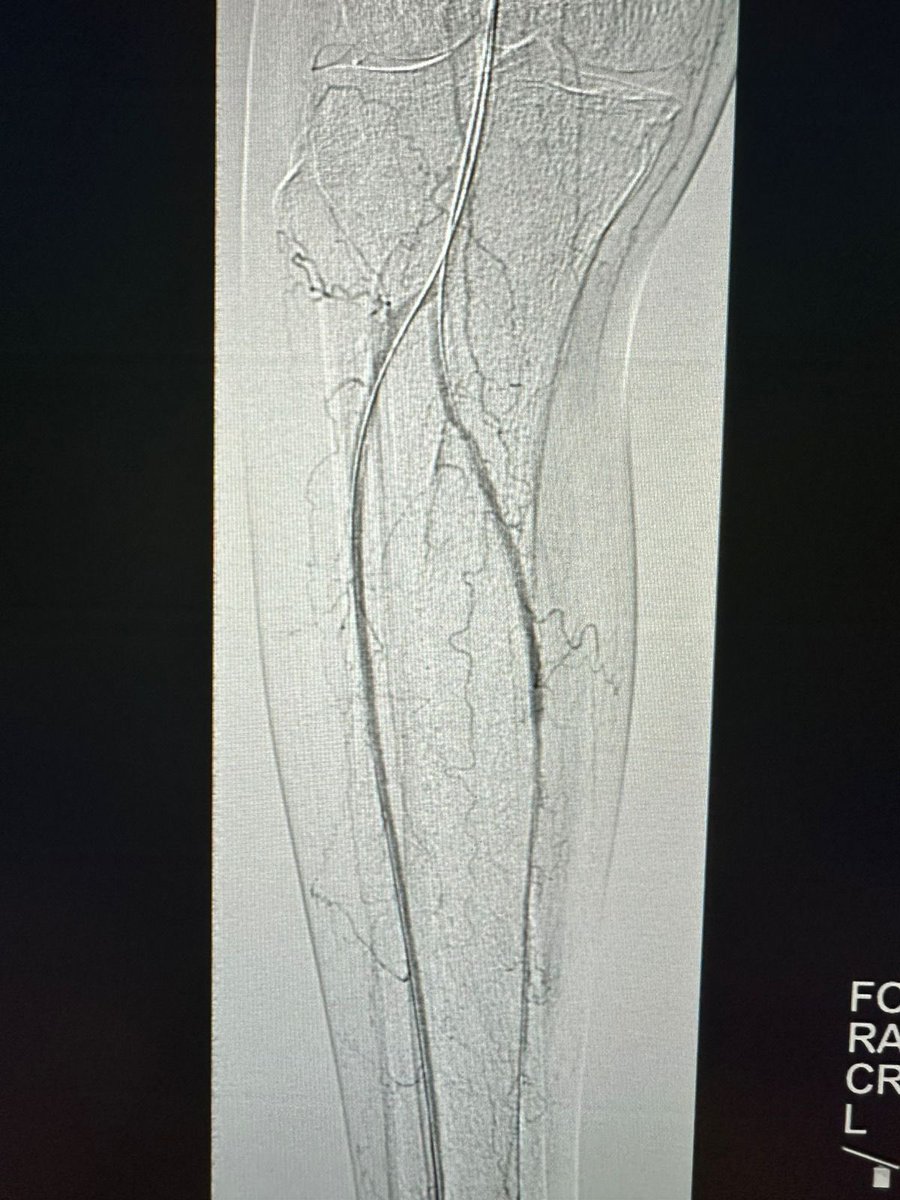

حالة من حالات نقص التروية الدموية الحاد مع وجود جرح غير ملتئم في القدم تم علاجها في وحدة #الأشعة_التداخلية بجامعة الملك سعود بالدخول من شرايين الفخذ والكاحل و إعادة فتح و توسيع الشرايين @ksumedicalcity @_KSU

د.سلطان رباح الحربي | Dr. Sultan R.Alharbi tweet mediaد.سلطان رباح الحربي | Dr. Sultan R.Alharbi tweet mediaد.سلطان رباح الحربي | Dr. Sultan R.Alharbi tweet mediaد.سلطان رباح الحربي | Dr. Sultan R.Alharbi tweet media

في وحدة #الأشعة_التداخلية بجامعة الملك سعود نقوم بتوفير أحدث التقنيات لعلاج القدم السكرية ونقص التروية. الدخول للشرايين يتم من الفخذ ، أو في بعض الحالات المتقدمة من الكاحل أو حتى من اخر القدم. بعض التقنيات لا توجد الا في أماكن قليلة جداً بالشرق الأوسط @ksumedicalcity @_KSU @ksu_medicine @FcmKsu